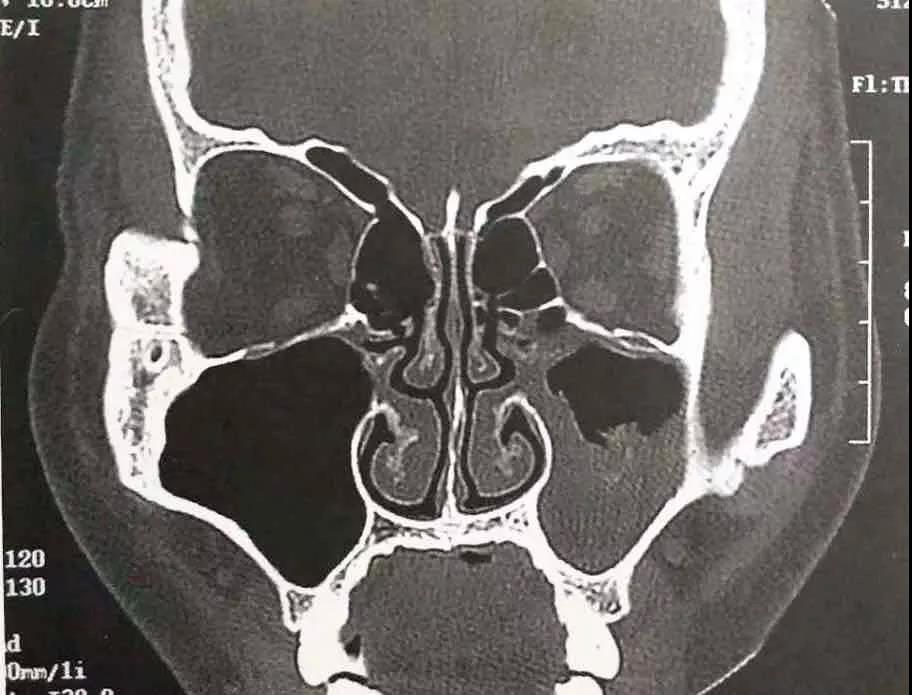

之后一個(gè)月,魏大叔仍然斷斷續(xù)續(xù)聞到難聞的異味,在雅安某醫(yī)院進(jìn)行副鼻竇CT檢查后,診斷為鼻竇炎。

(魏大叔CT圖示)